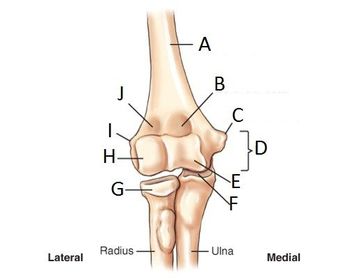

A. humerus B. coronoid fossa C. medial epicondyle D. humeral condyle E. trochlea F. trochlear sulcus G. radial head H. capitulum I. lateral epicondyle J. radial fossa